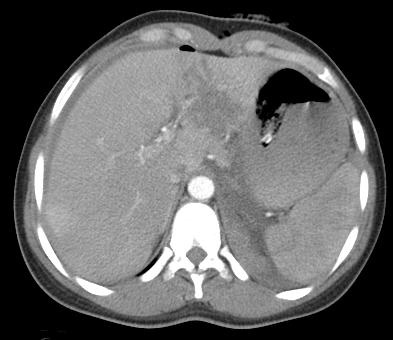

外伤后肝左叶实质出血 |

栓塞左肝外侧叶动脉分支(经验栓塞) |